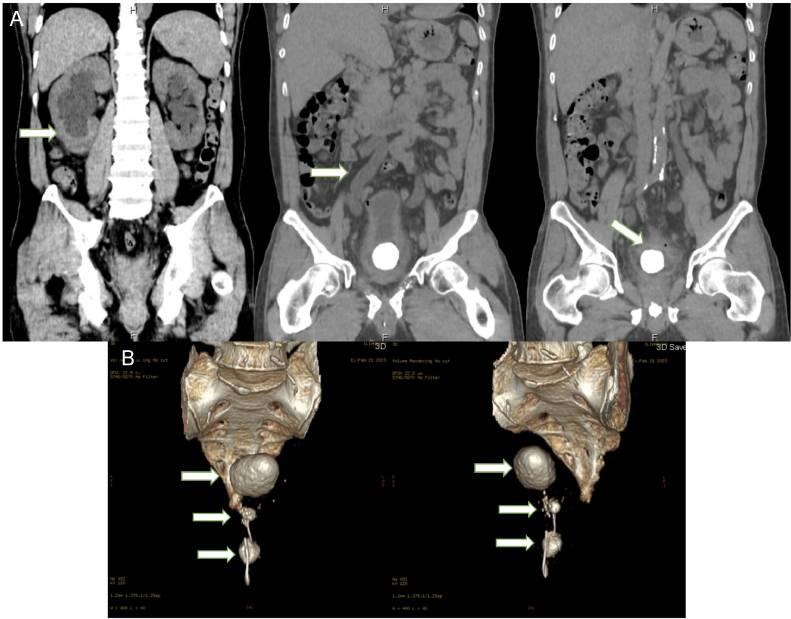

体格检查显示无耻骨上压痛、隆起或肿块。血液检查显示轻度贫血,血尿素氮升高为171 mg/dL(19.3-49.2 mg/dL),血肌酐升高为12.4 mg/dL,提示严重肾功能衰竭。尿液分析见白细胞和红细胞,提示尿路炎症。腹部X光片显示盆腔有一不透光异物及一个类似金属丝的线性不透光阴影(图1)。尿道造影显示充盈缺损和尿道扩张(图2)。CT扫描证实双侧肾积水和输尿管积水,以及大小为4.4×3cm的膀胱结石。大小为1.9×1.2cm的尿道结石也显著可见,并伴有类似金属丝的线性异物(图3)。CT扫描证实为梗阻性肾病。

图3 CT扫描显示双侧肾积水、输尿管积水、膀胱结石和尿道结石包裹异物